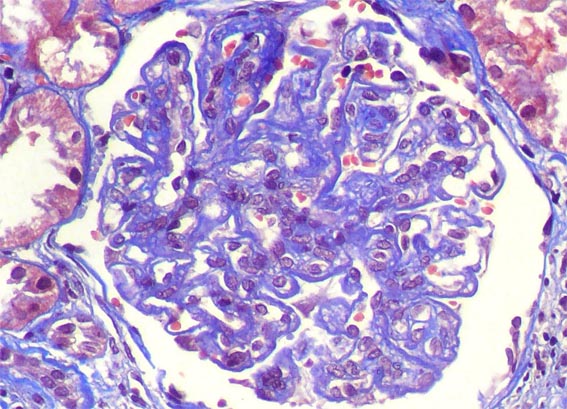

Figura 4.

Tricrómico de Masson, X400.

Figura 5.

El mismo glomérulo de la imagen anterior, amplificada. Tricrómico

de Masson, X400.